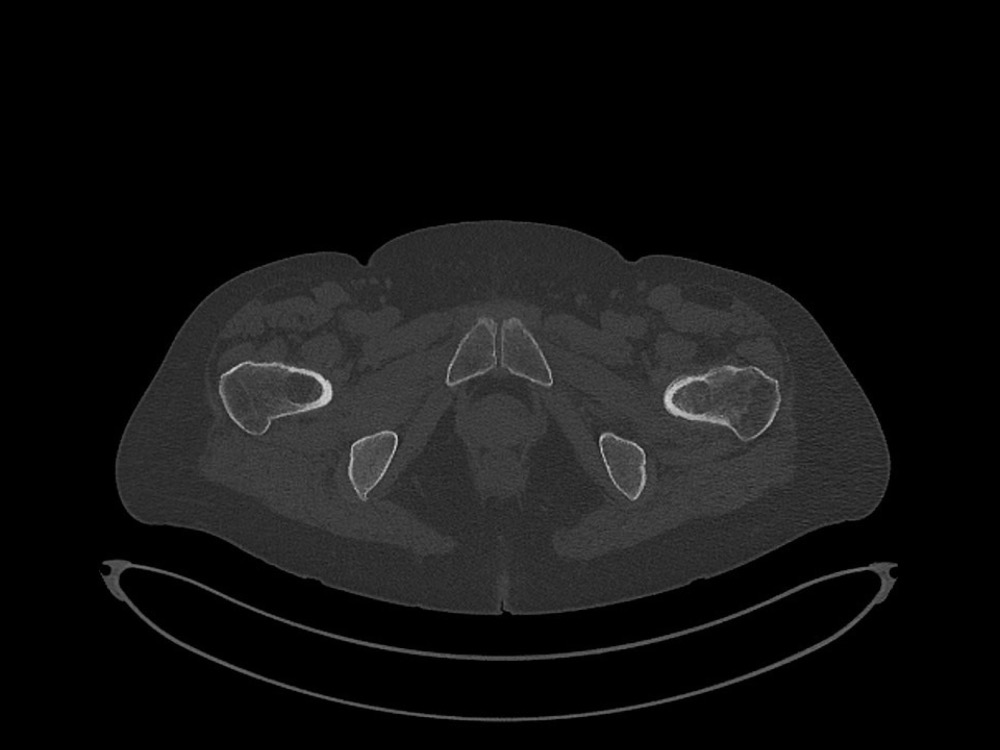

Douleurs de hanche

Linda Ouerd 06/11/2019